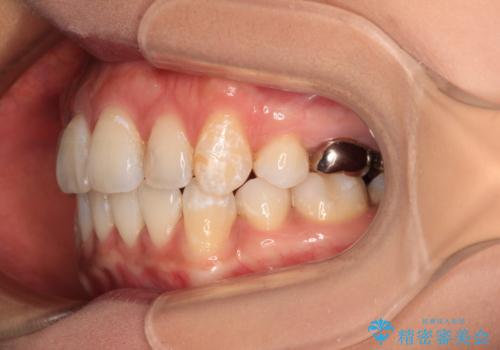

4本の歯を抜歯したことで、飛び出していた口元が引っ込み、横顔が大きく改善されました。